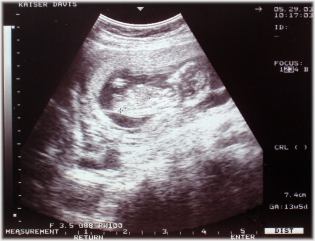

2003. május.29. (14. hét) Az első ultrahang felvétel